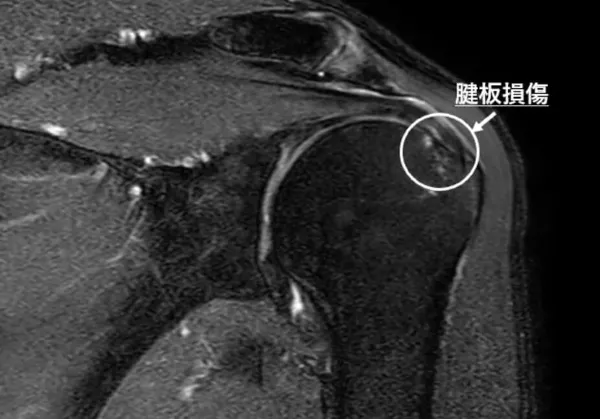

肩関節を支える腱板と呼ばれる筋肉群の腱が部分的または完全に断裂する状態です。主に肩への過度な負荷や加齢による原因で発生します。症状には肩の痛み、動かす際の制限、夜間痛があり、特に腕を上げる動作が困難になることが特徴です。治療方法は断裂の程度により異なり、軽度なら物理療法や薬物療法で改善を見込めますが、自然治癒は難しいとされています。